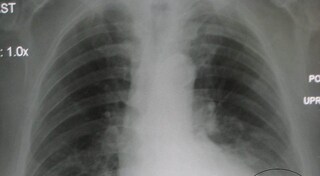

Corona Patient X Ray Image

Coronavirus Terrifying X Rays Show Covid 19 Patients Lungs Ravaged By Disease North Wales Live

Coronavirus What X Rays And Ct Scans Reveal About How Covid 19 Kills Science Tech News Sky News

Shocking X Ray Images Show Affect Of Coronavirus On Lungs Of Patients London Evening Standard